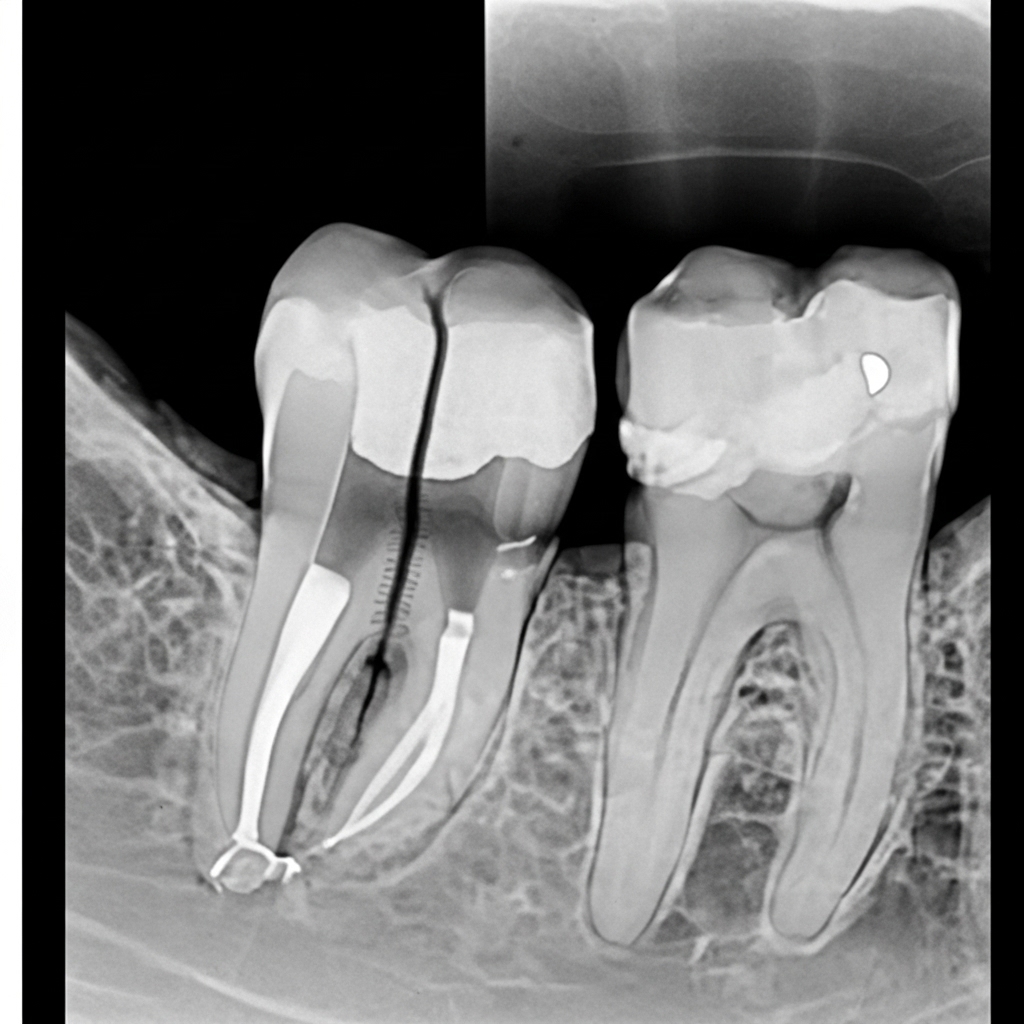

• Endodontia (Tratamento de Canal): Realizado de forma mecanizada em uma única sessão, totalmente indolor, para remoção da polpa dental inflamada ou necrosada.